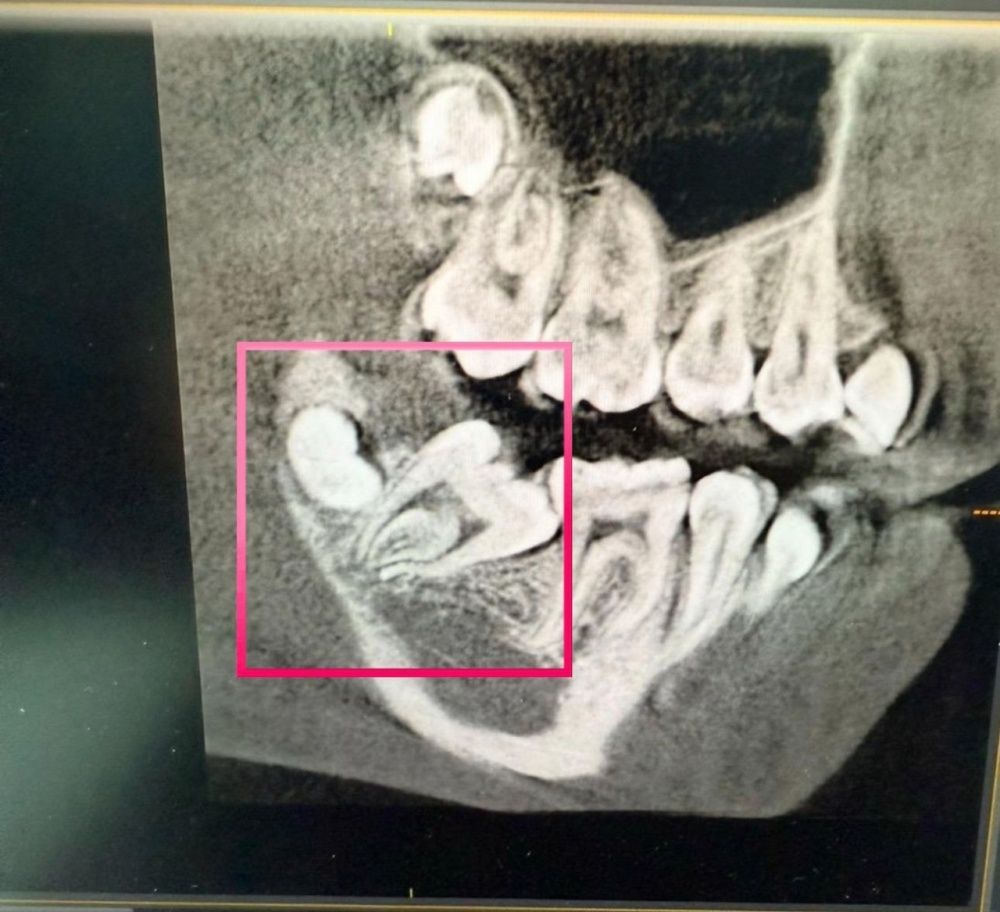

При проведении компьютерной томографии челюстей выявлено полуретенция (неправильное прорезывание) жевательного зуба 4.7, и зачаток зуба мудрости 4.8, который будет препятствовать дальнейшему лечению.